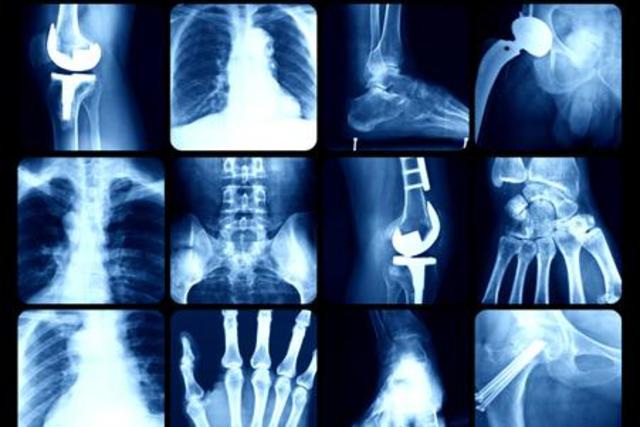

• Rayos X

Rayos X

Wilhelm Rontgen descubre los rayos X

• Tomografia Computarizada

Tomografia Computarizada

Housfield, crea la tomografía computadorizada el cual es un quipo que utiliza rayos X para dar diagnostico, creando imagenes transversales en el cuerpo.